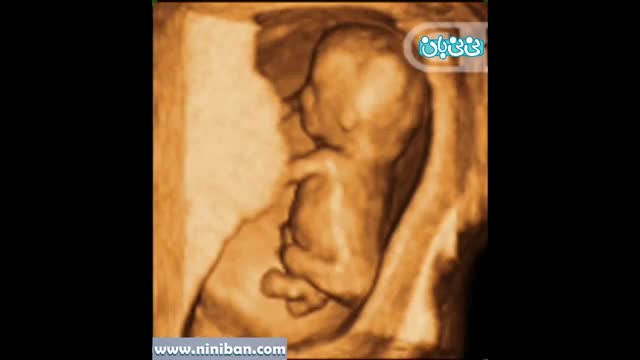

سونوگرافی چهار بعدی در بارداری هفته دوازدهم

۴ سال پیش

73343 بازدید